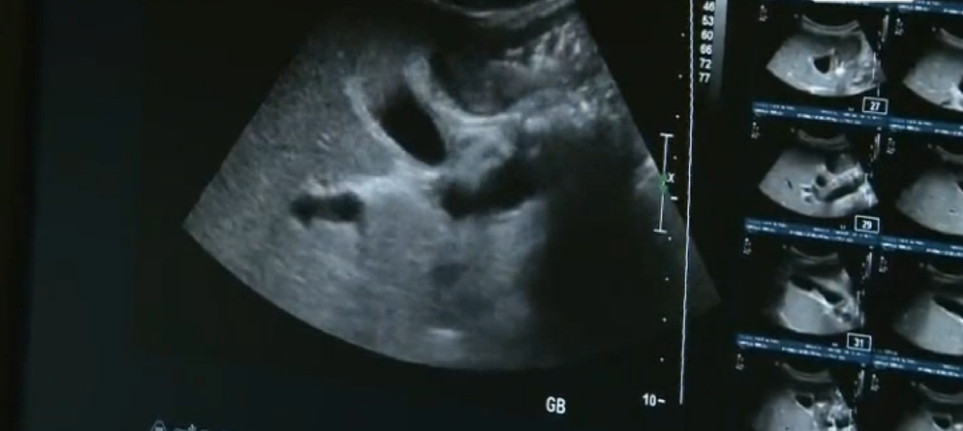

당뇨병과 만성 췌장염에 이어

현재 그는 간이 작아지면서 딱딱하게 굳는 간경화 상태까지 발생하기에 이르렀다.

이 상태에서 술을 더 마시면 생명까지 위태롭다는 경고를 담당 의사로부터 들어야 했다.